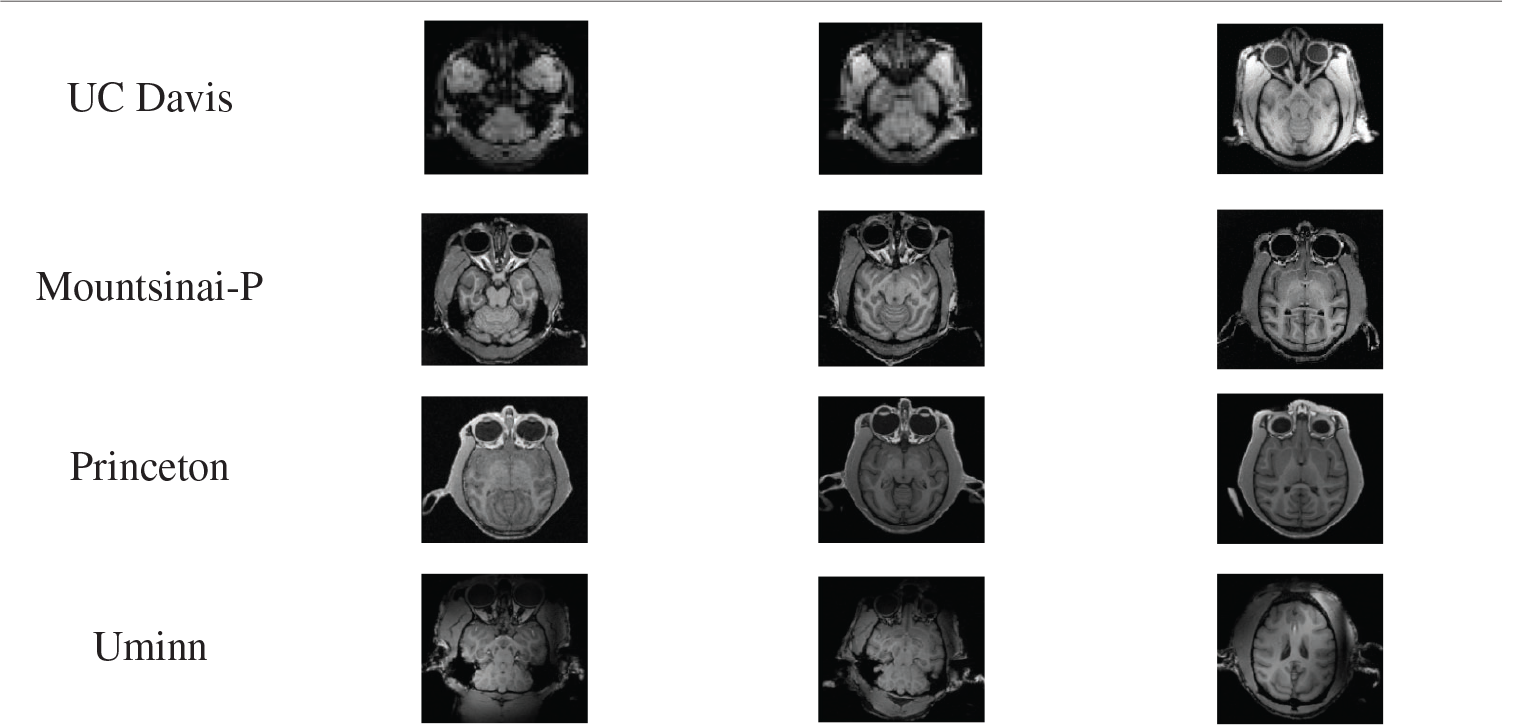

1. UC Davis Dataset. The data set collected data from 19 rhesus monkeys using the Siemens Skyra3T scanner. The data included structures T1 and T2, as well as task-state fMRI and dMRI. In this experiment, NMR data with structures T1 were used. All the 19 monkeys were females, ranging in age from 18.5 to 22.5 years. The weight distribution was 7.28-14.95kg. Scanning sequence parameters: voxel resolution = 0.3 × 0.3 × 0.3 mm, TE = 6.93 ms, TR = 15 ms, TI = 1100 ms, Flip Angle = 8°.

2. Mountsinai-P Dataset. Data of 9 macaques were collected by the Philips 3T scanner. The data included structures T1, T2, and dMRI. In this experiment, NMR data with structures T1 were used. The data set included 8 males and 1 female, with an age distribution of 3.4-8 years and a weight distribution of 4.7-7.42kg. The scanning sequence parameters were as follows: voxel resolution = 0.5 × 0.5 × 0.5 mm, TE = 6.93 ms, TR = 15 ms, TI = 1100 ms, Flip Angle = 8°.

3. Princeton Dataset. The data set used Simens Prisma VE11C 3T scanner to collect data from two rhesus monkeys. The data included structures T1, T2, dMRI, and task-state fMRI. In this experiment, NMR data with structures T1 were used. All the two macaques in the data set were male, with an age distribution of 3 years and a weight distribution of 4.7-5.5kg. Scanning sequence parameters were as follows: voxel resolution = 0.5 × 0.5 × 0.5 mm, TE = 2.32 ms, TR = 2700 ms, TI = 850 ms, Flip Angle = 9°.

4. Uminn Dataset. The data set was used to collect the data of 2 rhesus monkeys with Simens 7T scanner. The data included structures T1, T2, dMRI, and task-state fMRI. In this experiment, NMR data with structures T1 were used. All the two macaques in the data set were female, and their age distribution was over 10 years old. The scanning sequence parameters were as follows: voxel resolution = 0.3 × 0.3 × 0.3 mm, TE = 3.65 ms, TR = 2500 ms, TI = 1100 ms, Flip Angle = 7°.

Tab. 4 below shows some data of the above four experimental data sets.

Table 4: Experimental data set

Experiment one: The ce-LevelSet of the model in this paper was applied to UC Davis, Mountsinai-P, Princeton and Uminn, respectively, to verify the feasibility of the model in this paper. The default parameters of the model in this paper are: time step

Tab. 5 shows the results of monkey brain tissue extraction after the model was applied to four sets of UC Davis, Mountsinai-P, Princeton and Uminn, and it can be found that the model applied to four different data sets in this paper can achieve complete extraction of monkey brain tissue, with good extraction effect.